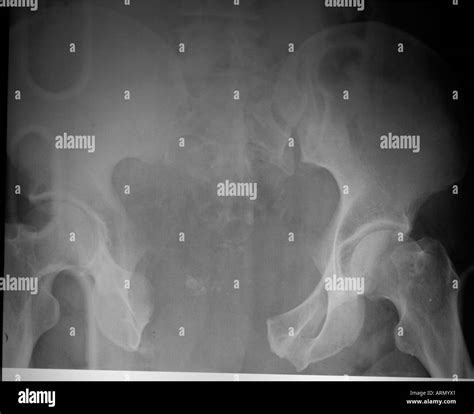

Open Book Fracture Pelvis

An open book fracture pelvis is a medical emergency that occurs when the pelvic ring is disrupted, typically due to high-energy trauma such as a motor vehicle accident or a fall from a significant height. This injury is technically classified as an anteroposterior compression (APC) fracture. The term "open book" describes the way the pelvic bones pull apart like the pages of a book being opened, which results in the pubic symphysis widening. Because the pelvis protects vital organs, major blood vessels, and nerves, this type of fracture carries a high risk of life-threatening internal hemorrhage and requires immediate specialized care.

The human pelvis is a strong, ring-shaped structure that supports the upper body and protects the pelvic viscera. When a massive force is applied to the front of the pelvis, it causes the pubic symphysis to separate. This disruption of the pelvic ring can occur in various degrees, classified by the Young-Burgess system, which assesses the severity of the damage based on the mechanism of injury.